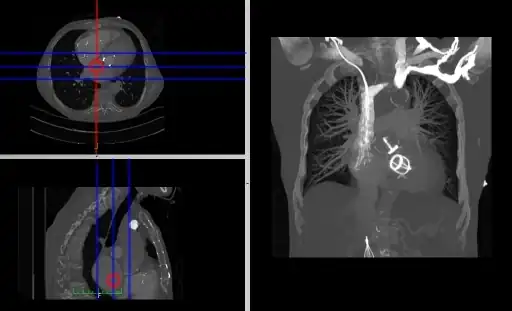

- Coronal and sagittal reconstructions are referred to as Orthogonal MPRs because the perspectives generated are from planes of image data which are at right angles to each other. Composite MPR displays can be generated so that linked cursors or crosshairs can be used to locate a point of interest from all three perspectives, as illustrated in these images:

![]() |

- This form of image presentation is sometimes referred to as a TCS display – implying the viewing of Transaxial, Coronal and Sagittal slices. It can be combined with the slice projection methods we discussed earlier, as illustrated in the two sets of images below, where the blue lines highlight the limits of the coronal projections:

- Here the plane can be defined in, say, the axial images (red line, top left) and a maximum intensity projection (the limits used are highlighted by the blue lines), for example, can be displayed for the reconstructed plane (right). This technique is useful when attempting to generate perspectives in cases where the visualization of three-dimensional structures is complicated by overlapping anatomical detail.